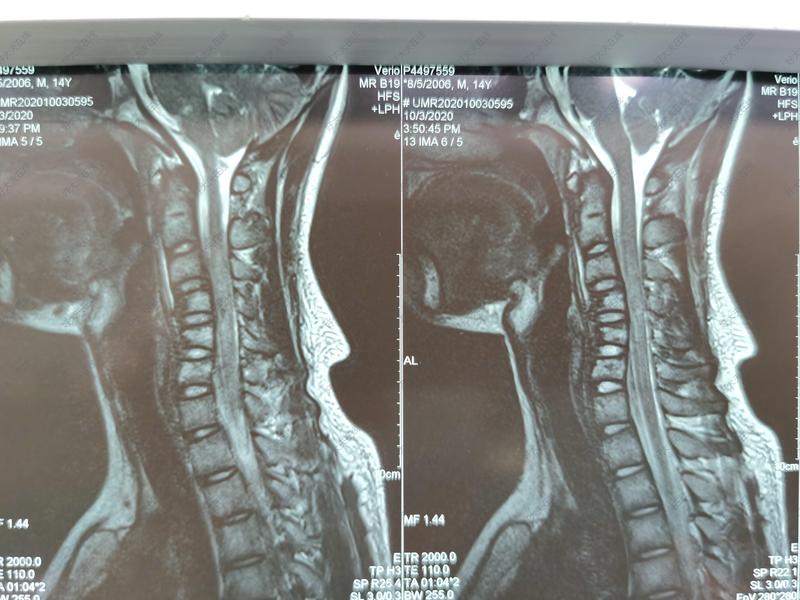

颈椎后路减压固定术

治疗前14岁的男性患者,于2020年国庆节期间不慎发生车祸伤,致颈椎外多发骨折并脊髓损伤,术前四肢瘫痪;入院后,急诊手术,采用颈椎后路椎弓根螺钉固定,半椎板切除减压。彻底减压,为患者脊髓功能的恢复创造条件;保留一侧椎板,是为了后期患者颈椎功能更好;颈椎全椎弓根螺钉固定,即刻重建了颈椎的稳定性。治疗后治疗后30天积极手术治疗,今早进行康复功能锻炼,患者术后一个月已经恢复行走功能。治疗后3天颈椎全椎弓根螺钉固定,具备坚强的力学强度,较好的复位了骨折椎体高度,以及颈椎生理前凸;术后第二天即可开始进行康复功能锻炼,初进脊髓神经功能的恢复。